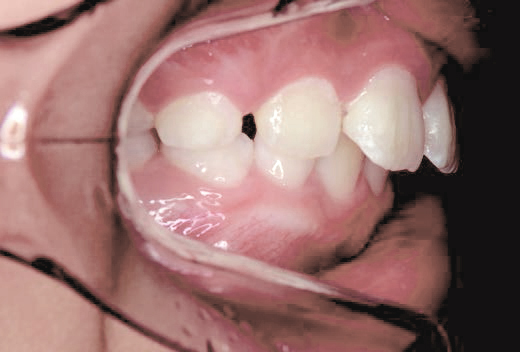

鼻がつまりやすく、口呼吸をしているために上あごが狭い状態でした。また上の前歯がかなり前へ傾いているため、お口をきちんと閉じていることができません。さらに、下の前歯もでこぼこしていました。